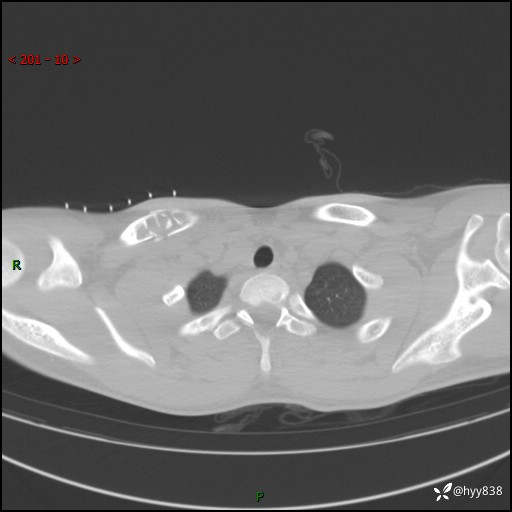

CT